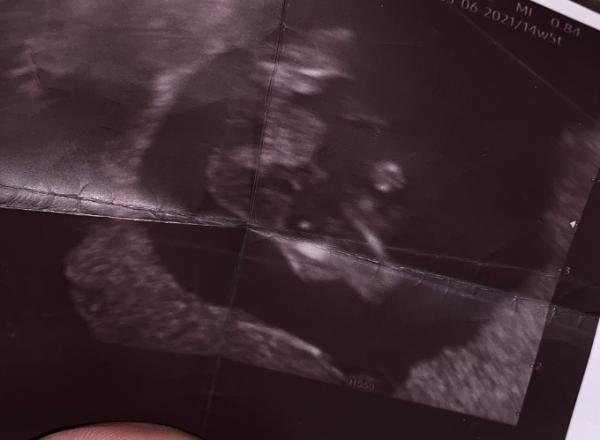

Hallo liebe Community, Ich bin in der 15 ssw und hatte vor paar Tagen einen Ultraschall Termin. Meine Ärztin Vermutet einem Jungen. Jetzt wollte ich mal wissen was ihr von diesem Bild hält. Vielleicht ist das zwischen den Beinen ja eine Nabelschnur ? Vielen Dank für Eure Bemühungen :-)

Hallo, mich schaut es schon nach Jungen an aber wer weiss es ist ja noch früh .... Lg